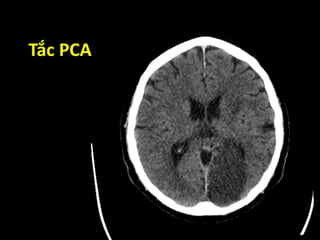

Tắc PCA

Các dấu hiệusớm chẩn đoán nhồi máu não trên CT Scan • Dấu tăng tỉ trọng động mạch não  “dot sign”  “hyper dense” – dấu dây thừng • Dấu hiệu gây ra bởi hiện tượng phù não  Mất phân biệt xám-trắng  Mất dải ruy-băng thùy đảo  Xóa mờ nhân đậu  Mờ rãnh Sylvius  Mất các rãnh não

• #65 Sinh ra bởi tắc các nhánh của ĐM não giữa.